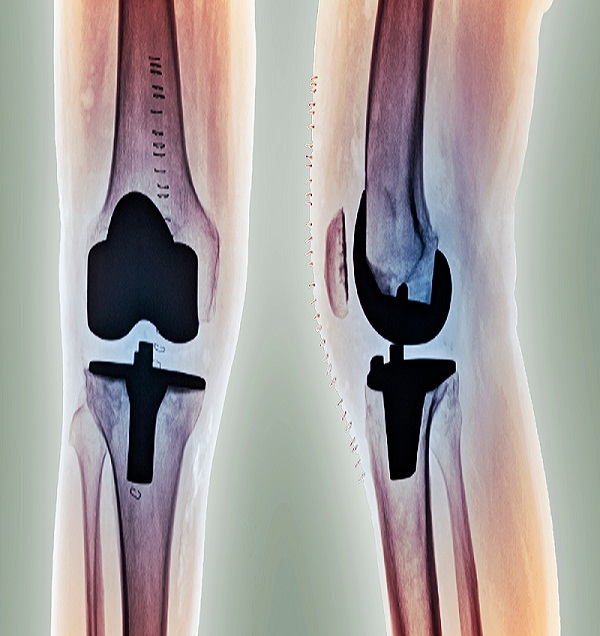

Knee Joint Replacement

Knee replacement surgery is often a last resort treatment for an injured or damaged knee joint. This procedure takes a few hours, but recovery and rehabilitation can last months. Some of the risks of this procedure are infection, nerve damage, and knee stiffness.

Knee joint replacement is a procedure that involves replacing an injured or ailing knee with an artificial joint, or prosthesis. Another name for this procedure is knee arthroplasty. Knee replacements are a very common surgery.

The prosthesis is made of metal alloys, plastics, and polymers. It mimics the function of a knee. Replacement knees can fit your needs and specifications. When selecting a prosthetic knee, your doctor will take into account your: